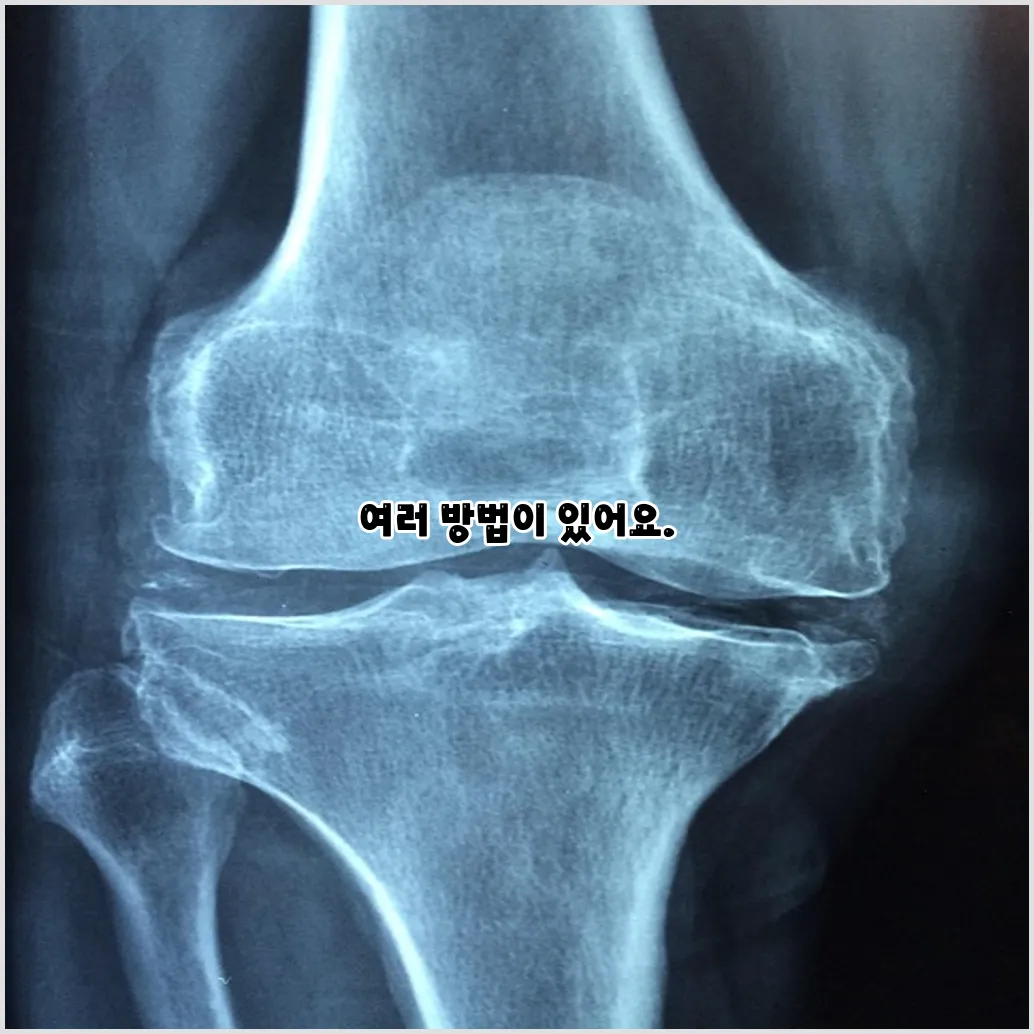

관절염 통증은 많은 사람들에게 일상 생활에 큰 영향을 미치는 문제입니다. 관절염은 관절의 염증과 통증을 일으키며, 나이가 들면서 더욱 흔하게 나타나는 질환입니다. 그렇다면 관절염 통증을 완화하고 관리하는 방법에는 어떤 것들이 있을까요? 이번 포스팅에서는 관절염 통증 완화를 위한 다양한 방법과 치료법, 그리고 자연 요법을 소개하겠습니다. 함께 이 주제를 깊이 탐구해 보도록 하겠습니다.

관절염은 일반적으로 두 가지 유형으로 나눌 수 있습니다. 첫 번째는 퇴행성 관절염으로, 노화와 함께 발생하며 관절의 연골이 닳아 없어지는 현상입니다. 두 번째는 류마티스 관절염으로, 면역 시스템의 이상으로 인해 관절이 염증을 일으키는 질환입니다. 이러한 다양한 원인은 통증을 발생하게 하며, 이는 우리의 삶의 질을 떨어뜨릴 수 있습니다.

관절염 통증 완화 방법

관절염 통증을 완화하기 위한 방법에는 여러 가지가 있습니다. 사람마다 다르게 반응할 수 있지만, 여러 접근 방식을 통해 통증을 경감시킬 수 있습니다.